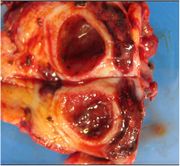

[黄色肉芽腫胆嚢炎] 手術:胆嚢摘出術(結腸切除術併施)

血液検査にて炎症反応の上昇を認め、精査の結果、急性胆嚢炎と診断。胆嚢摘出術(結腸切除術併施)を施行した。病理結果は黄色肉芽腫胆嚢炎であった。

摘出検体画像